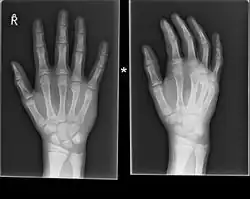

A healed fracture of the neck of the 5th metacarpal

Prognosis for these fractures is generally good, with total healing time not exceeding 6 weeks. The first few weeks will show significantly reduced overall swelling, with improvement in clenching ability showing up first.[8] Ability to extend the fingers in all directions appears to improve more slowly; hard casts are sometimes required, and along with soft casts or splints when removed will need physical therapy[3]

For Boxer's fracture one sees that closed management of neck fractures with less than 70 degrees of angulation have a very high degree of function[8]